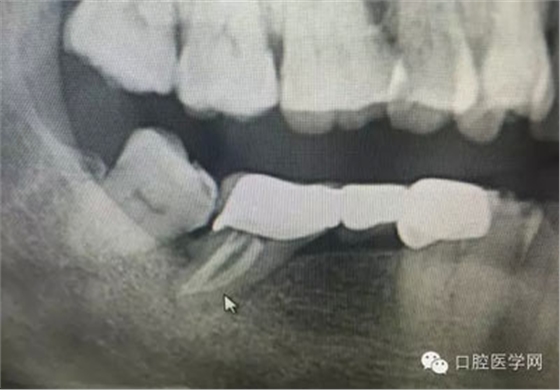

根管再治療是我們比較頭疼的,尤其是那些冠修復(fù)過(guò)的,我們有很多的麻煩需要去溝通,比如可能導(dǎo)致的側(cè)穿、可能沒有看到的腐質(zhì)、可能導(dǎo)致的崩瓷,或者是后期可能出現(xiàn)冠折......這些需要我們和患者好好的溝通。全瓷冠還好些,金屬冠根測(cè)的時(shí)候很是麻煩,總之我們做修復(fù)的時(shí)候不要單純的追求速度,追求效益,適當(dāng)?shù)淖⒁庀挛覀兊幕A(chǔ)治療和設(shè)計(jì)。

這是一例外院樹脂修復(fù)后十個(gè)月出現(xiàn)牙髓炎癥狀的患者。遇到這樣子的患者大家會(huì)怎么做,證明選擇,還有就是可做可不做治療的如何去平衡。